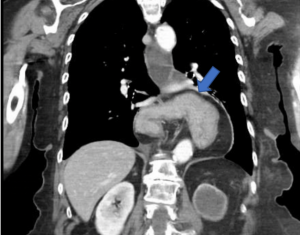

Ιατρικό Case Revision αντιπαλινδρομική επέμβαση Γυναίκα ασθενής 71 ετών προσήλθε στο ιατρείο μας με βαριά συμπτώματα γαστροοισοφαγικής παλινδρόμησης (ΓΟΠΝ). Η...